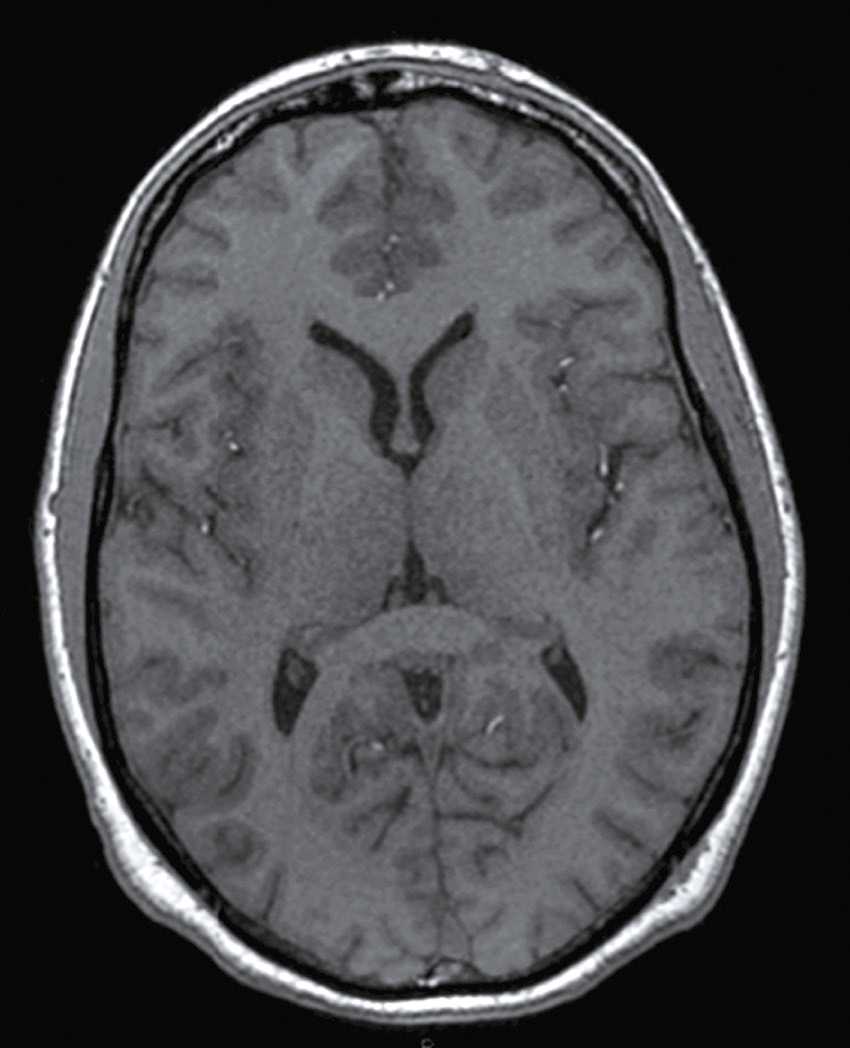

Une nouvelle IRM cérébrale est réalisée devant cette diplopie. Décrivez le cliché (fig. 31.1).

L'image montre une coupe transversale d'un cerveau humain obtenue par imagerie par résonance magnétique (IRM). Cette image est une vue axiale, ce qui signifie qu'elle est prise horizontalement à travers le cerveau. On peut observer les différentes structures cérébrales, y compris la matière grise et la matière blanche. Les ventricules latéraux, qui sont des cavités remplies de liquide céphalo-rachidien, sont visibles au centre de l'image. Les zones plus claires autour des ventricules peuvent indiquer des anomalies ou des lésions, souvent associées à des conditions neurologiques comme la sclérose en plaques. Les contours du cerveau sont bien définis, et les différentes régions du cortex cérébral sont clairement visibles. Cette image est intéressante car elle permet aux médecins de diagnostiquer et de surveiller diverses maladies neurologiques en visualisant les structures internes du cerveau avec une grande précision. L'IRM est une technique non invasive qui utilise des champs magnétiques et des ondes radio pour produire des images détaillées des organes et des tissus internes, ce qui est crucial pour la détection précoce et le traitement des maladies cérébrales.

- A coupe sagittale

- B séquence T1

- C hypersignaux de la substance blanche périventricu-laire

- D hypersignaux du tronc cérébral

- E hypersignaux juxtacorticaux